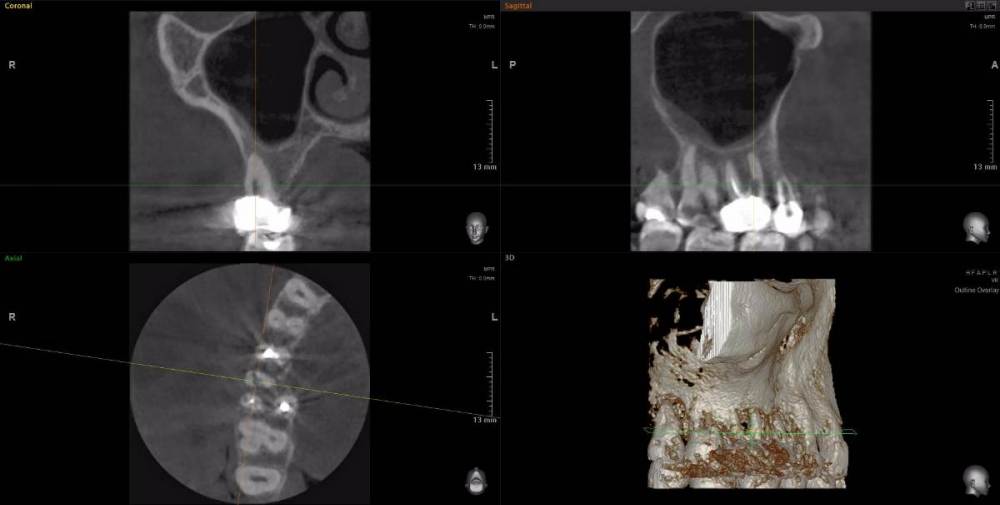

Рабин Опубликовано 18 мая, 2021 Автор Поделиться Опубликовано 18 мая, 2021 Добрый день! Сделала КТ этого зуба, как вы просили... https://cloud.mail.ru/stock/kkbze24nzBzfEqnUbdPwtsei Видите ли вы воспаление на нём и можно ли его спасти? Интересует также соседний 15 зуб. Спасибо! Ссылка на комментарий

wladdX Опубликовано 18 мая, 2021 Поделиться Опубликовано 18 мая, 2021 (изменено) Зуб 16, на мой взгляд, придётся удалить. Зуб 18 тоже Зуб 15 вроде бы и не вызывает особых восторгов, но и явного неприятия тоже. Изменено 18 мая, 2021 пользователем wladdX 2 Ссылка на комментарий

red_butler Опубликовано 20 мая, 2021 Поделиться Опубликовано 20 мая, 2021 18.05.2021 в 23:24, wladdX сказал: Зуб 16, на мой взгляд, придётся удалить. +1 Ссылка на комментарий

wladdX Опубликовано 29 мая, 2021 Поделиться Опубликовано 29 мая, 2021 18 - там приличных размеров корневая гранулёма, излечить нереально 1 Ссылка на комментарий